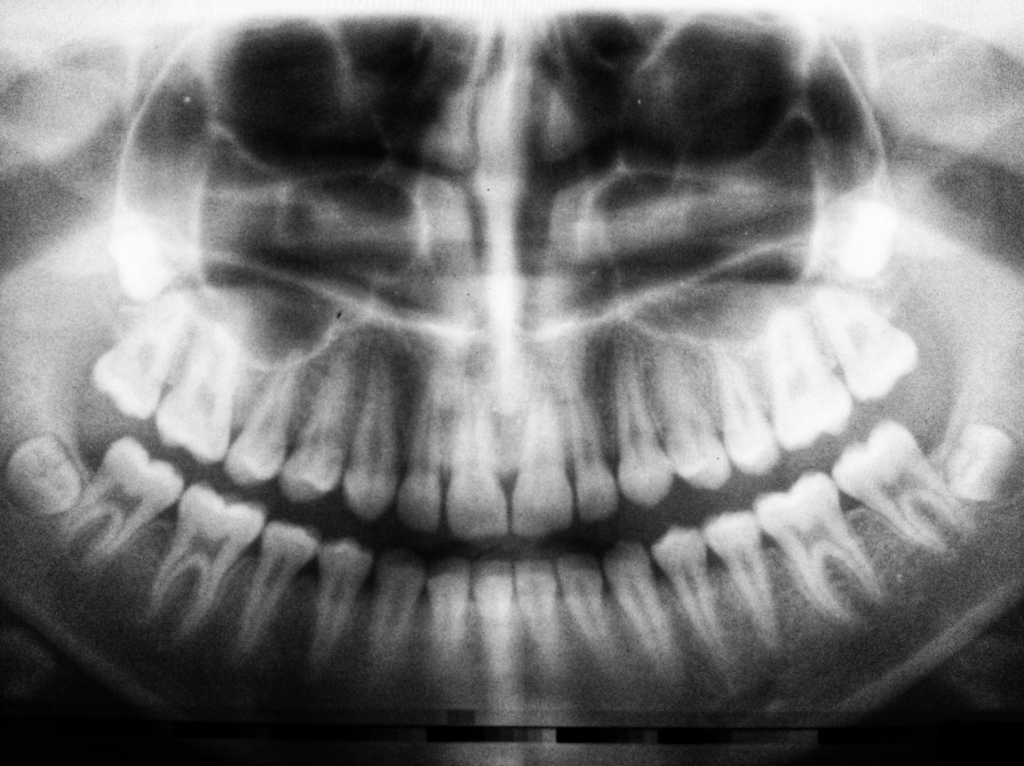

The fundamental factor when it comes to placing an implant is the existence of sufficient bone to be able to support the base of the dental implant. Therefore, in the first appointment, a radiographic and clinical examination will be made to determine if you have the capacity to deal with this device without the body rejecting it.

For the 3D radiographic examination there is a specific examination for patients who are possible candidates for implant placement, and all this is done through a computer and a specialist in this machinery. This exam is absolutely necessary, since it gives the specialist all the information he needs about your oral cavity, for example, the thickness of the bone where the implant will be placed, the height, the position of your nerves and arteries in the area and allows to plan how the procedure will be done, since each body is unique and each procedure is individual.